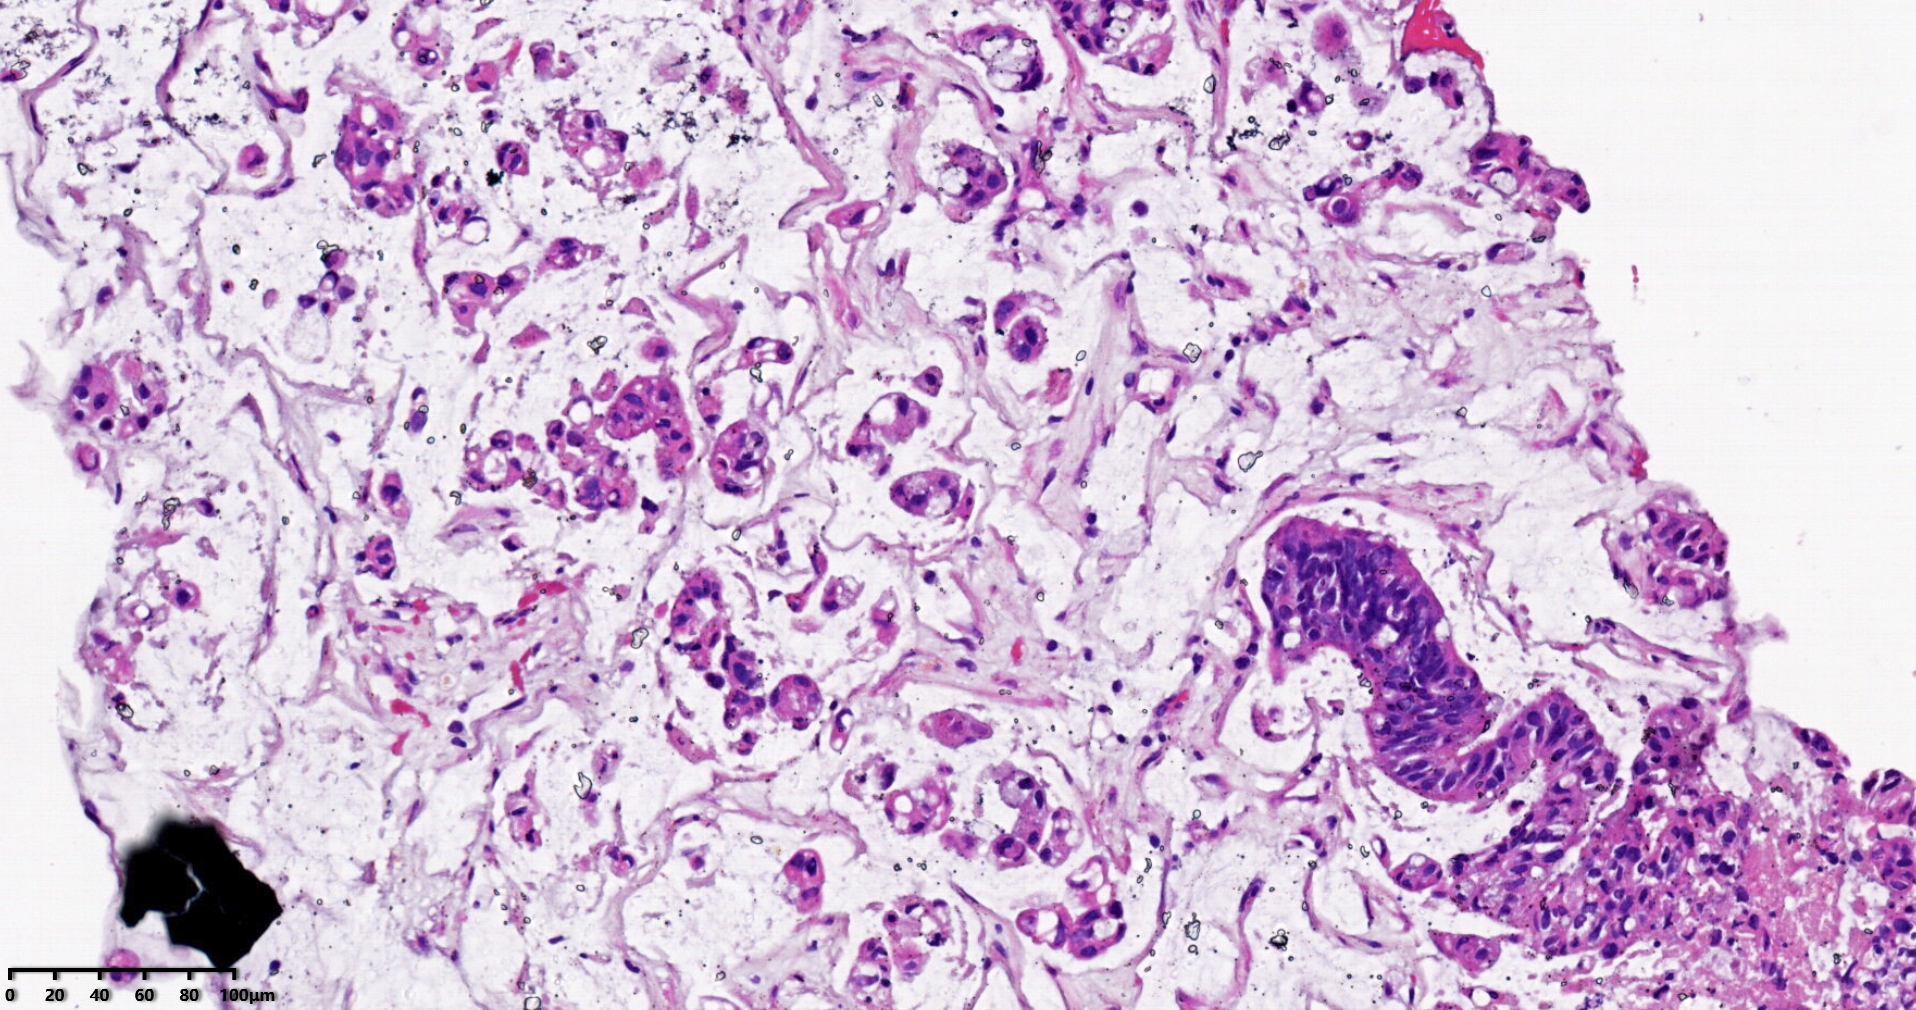

标本名称肝脏穿刺

大体所见灰白灰红色穿刺活检组织两条,长1.7-1.9cm,直径0.1-0.2cm。

考虑符合:肝内胆管癌

• rys114:  老师,免疫组化ck7-,ck20+,支持诊断吗?

• whyang315:  当然!

考虑转移性黏液腺癌,消化道来源可能,建议做免疫组化,排除胆管源性。